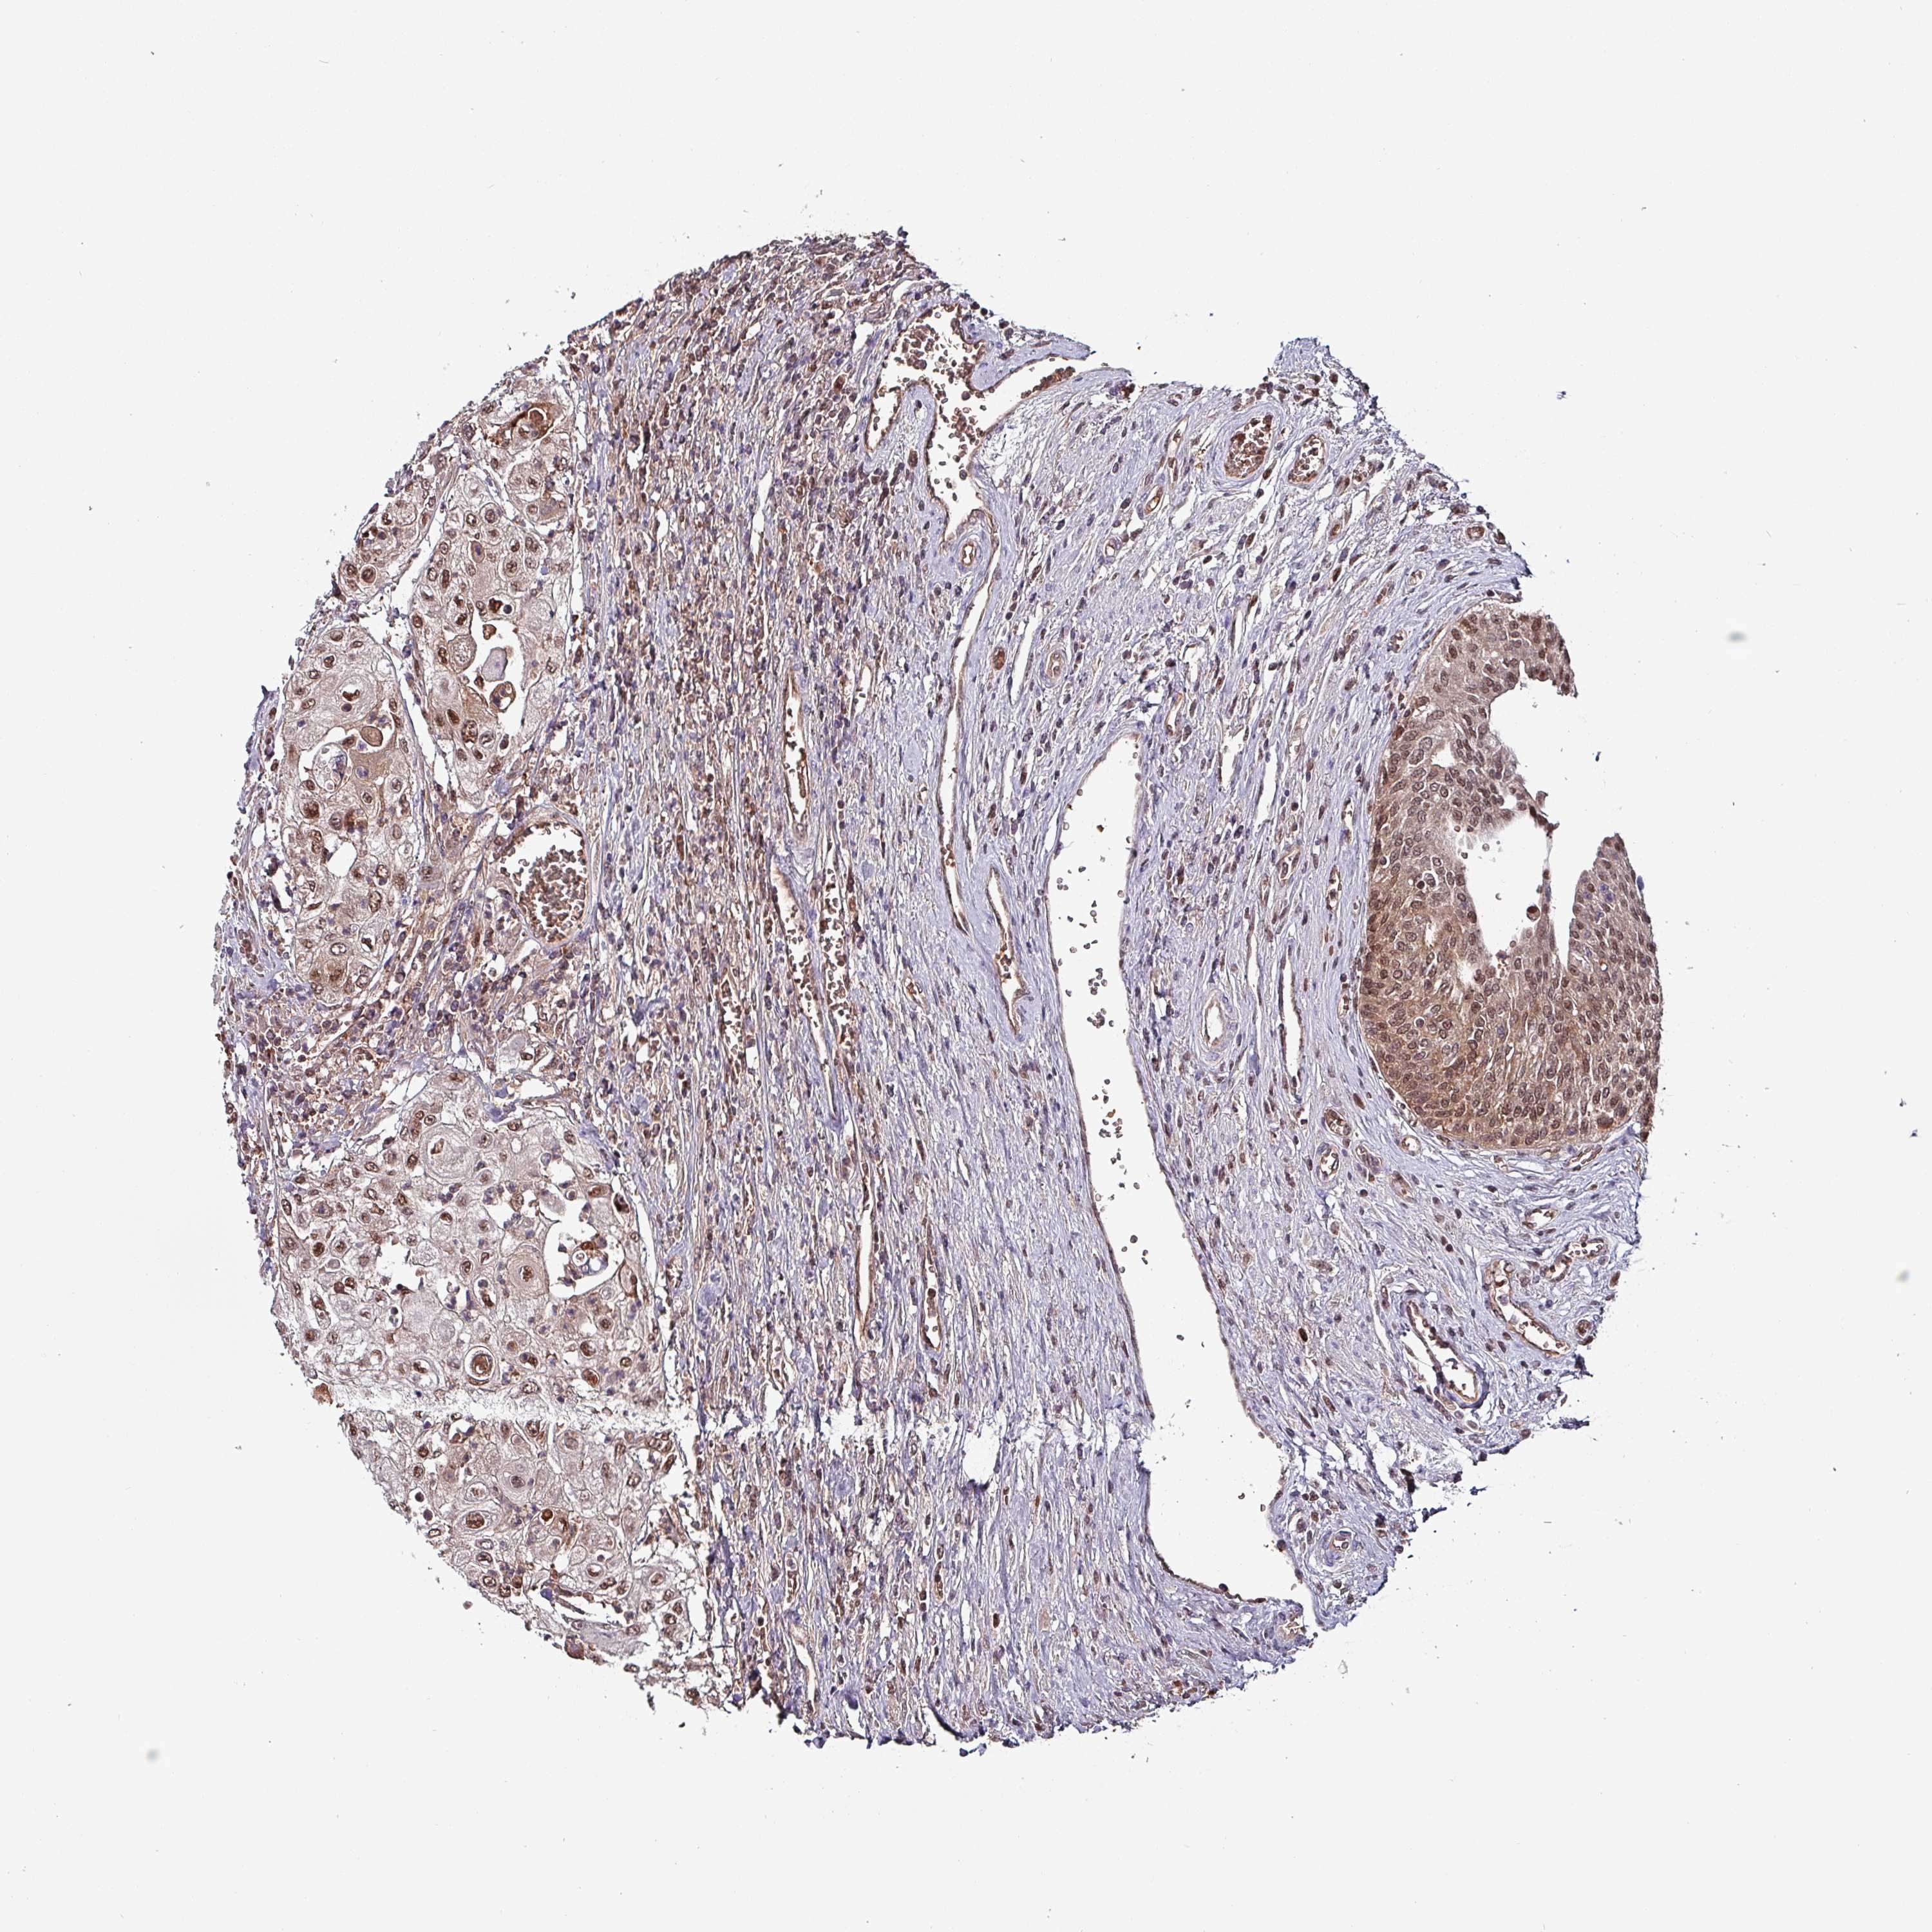

UROTHELIAL CANCER - Protein expressioni

A mouse-over function shows sample information and annotation data. Click on an image to view it in a full screen mode. Samples can be filtered based on level of antibody staining by selecting one or several of the following categories: high, medium, low and not detected. The assay and annotation is described here.

Note that samples used for immunohistochemistry by the Human Protein Atlas do not correspond to samples in the TCGA dataset.

Antibody stainingi

Antibody staining in the annotated cell types in the current human tissue is reported as not detected, low, medium, or high, based on conventional immunohistochemistry profiling in selected tissues. This score is based on the combination of the staining intensity and fraction of stained cells.

Each image is clickable and will lead to virtual microscopy that enables deeper exploration of all samples and also displays staining intensity scores, fraction scores and subcellular localization as well as patient and tissue information for each sample.

Antibody HPA046995

Antibody HPA050327

Staining

High

Medium

Low

Not detected

Intensity

Strong

Moderate

Weak

Negative

Quantity

>75%

75%-25%

<25%

None

Location

Nuclear

Cytoplasmic/membranous

Cytoplasmic/membranous,nuclear

Urothelial carcinoma, High grade

Urothelial carcinoma, Low grade

Urothelial carcinoma, NOS